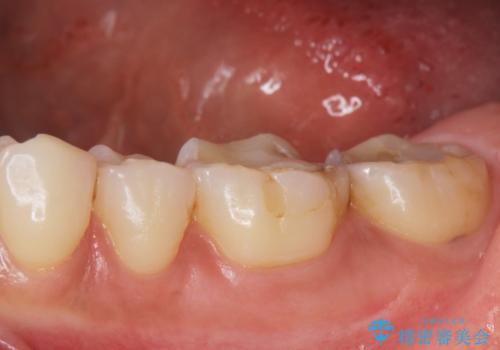

- 歯が黒くて虫歯じゃないかと心配して来院。

過去にプラスチックの樹脂で治療されており、歯とプラスチックの隙間から虫歯が進行していました。

拡大鏡下で虫歯を除去し、詰め物にて治療しました。

一番奥の歯は歯の高さが足りない、噛む面を覆う面が広くなってしまい、セラミックの詰め物だと割れるリスクが高くなってしまうので手前はセラミックインレー奥の歯はゴールドインレーにて治療しました。